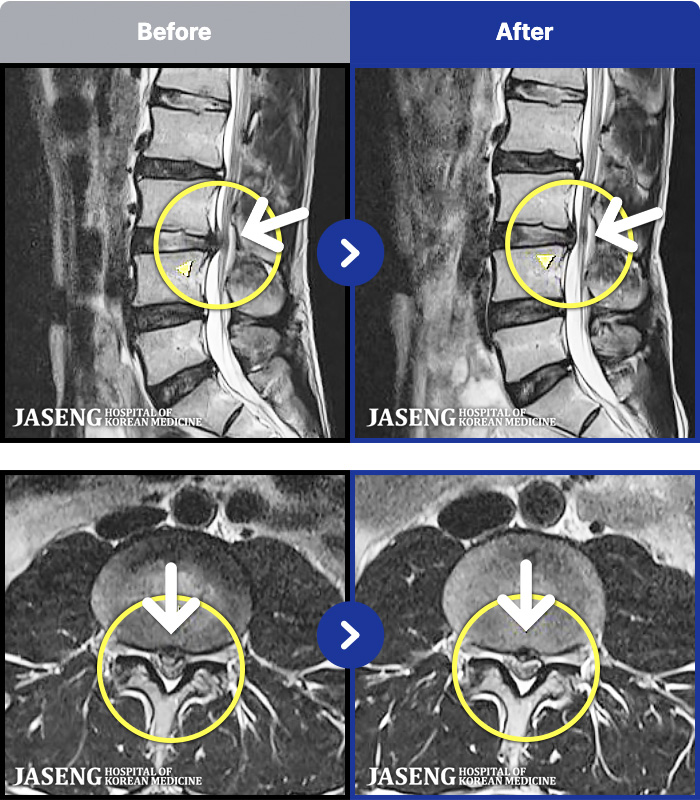

1,299 MRI ũ ʸ Ȯϼ.

[] 23.11.11~25.06.04